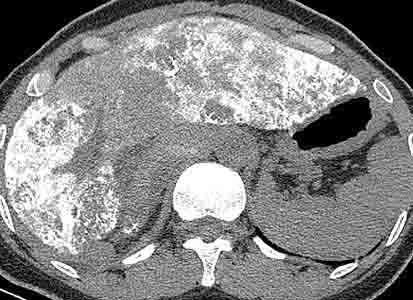

患者女性,43岁,肝癌tace治疗后出现胸闷不适.

动静脉瘘,栓塞剂经瘘口进入肝静脉--下腔静脉--右心房--右心室--肺动脉--沉积于肺内.

原发性肝癌进行栓塞治疗时,若肝动脉造影显示肿瘤侵犯肝静脉,且有明显的肝动静脉瘘,则使用碘油乳剂就不妥当,因为大量碘油可通过瘘道进入肺部,引起肺栓塞的并发症。

此时应在抗癌药物灌注后,先注入明胶海绵条阻塞动静脉瘘,或经颈静脉穿刺置放球囊导管于肝静脉,暂时性阻断肝静脉血流后再考虑用碘油乳剂栓塞,栓塞后加用明胶海绵。

国内颜志平等报道:动物实验表明,碘化油进入肺部致死量约为0.5ml/ kg ,少量碘化油进入肺部可通过肺部吞噬细胞进行“消化”,故少量碘化油进入肺部后一般经过对症处理后,一般不会遗留明显并发症。